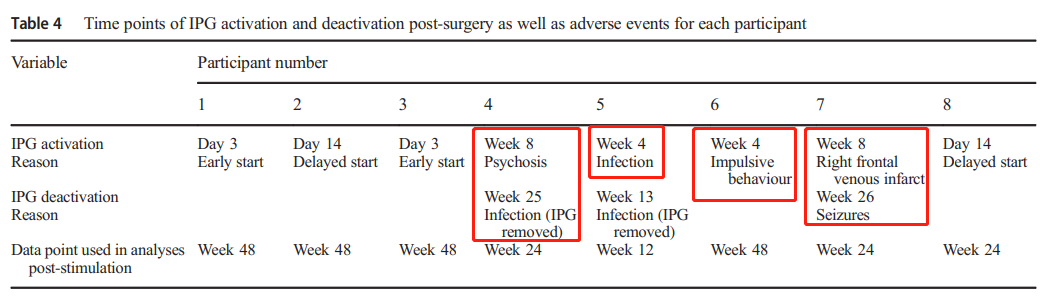

一半的患者出现了不良反应(如下表)。4号5号患者由于感染需要将IPG移除。4号患者在手术后3天出现精神症状。8号出现了右额静脉梗塞,并伴有斑点状的出血性改变,术后1天造成短暂的左侧肢体无力,偏瘫在3周后完全缓解,该患者在手术后26周有两次癫痫发作,需要停用IPG。6号患者在术后回家后的3周内表现出鲁莽的冲动行为,在术后回家后的3个星期里,IPG的激活被推迟了一个月。作者对此的解释是,4号6号的不良反应发生在IPG激活以前,可能是围手术期压力(perioperative stress)导致,并且4号入院时隐瞒了精神分裂症病史。8号产生的不良反应属开颅手术已知风险,4号5号的感染若使用万古霉素而不是常规的预防性抗生素,应该避免。